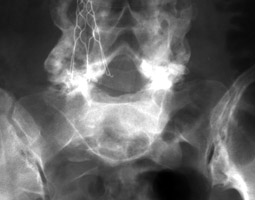

Frontal and lateral radiographs of the lumbar spine revealing anterolisthesis of the L5 vertebral body with the typical inverted Napoleon Hat sign. This sign is reserved for spondylolisthesis of the L5 vertebral body. With a case of spondylolisthesis, the AP radiograph will reveal the anterior border of the transverse process in continuity with the anterior border of the body of the same vertebrae. This continuous anterior border of the L5 vertebrae will be projected against the shadow of the sacrum, and appear as an upside-down (or inverted) Napoleon hat.

Lateral Lumbar Spine - Click on the image for a larger versionAAP L-S spine - Click on the image for a larger versionB